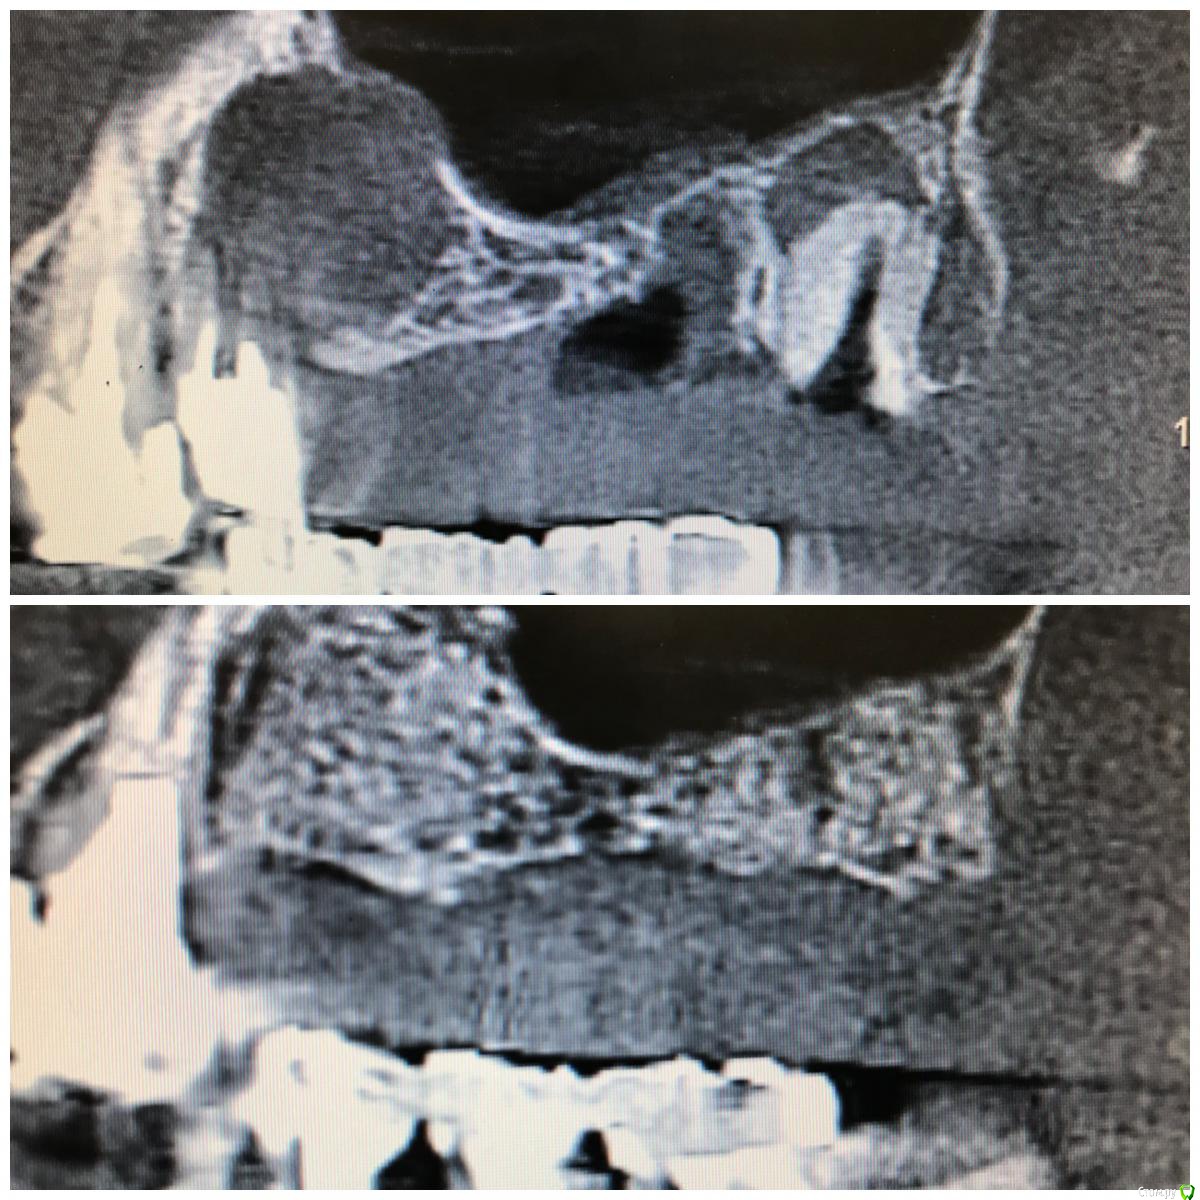

колесников Опубликовано 5 декабря, 2017 Поделиться Опубликовано 5 декабря, 2017 Пациентка N обратилась с жалобами на «выбухание дёсны» в обл 24. На клкт однотогенные кисты в/ч и значительные деформации гребня. От имплантации в перспективе категорически отказалась,потому было решено провести лишь подготовку гребня под чсп ( хотя было желание сделать открытый синус в обл 16/26 доступом через кистозную полость). Удаление причинных зубов без откидывания лоскута,вылущивание и кюретаж. Дефекты заполнены кортикальным аллографтом Sureoss,перекрыто бугром на ножке и vip ст. Был сдан чсп. Повторный визит через 7 мес. На клкт коегде кистозный свод просел. Видимо не достаточно графта было оставлено. Гребень выраженный,широкий. Случай показательный в плане эффективности и стабильности консервации лунки,очевидно что чсп не оказывает деформирующкно влияния на аугментированый гребень. По поводу удалить и подождать или удалить,заполнить и подождать,еще Carlos отмечал ,что кистозное выбухание в пазуху надо использовать для получения объема в зоне предстоящей имплантации. PS.Неудачи встречаются. Они связаны с нарушением герметизма лунки: некроз лоскута,распад сгустка и инфицирование графта. У меня было 2 жестокие неудачи,в первом случае пациент активный курильщик,второй любитель коньяка. В обоих случаях дополнительно применялся A-PRF ,но даже он не смог противостоять такому деструктивному влиянию агрессивных сред. 3 Ссылка на комментарий